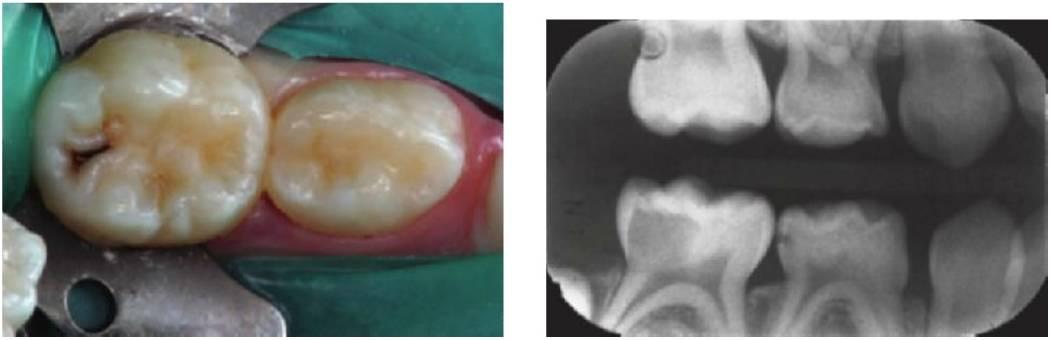

Las lesiones cariosas extensas y las preparaciones cavitarias asociadas alteran las propiedades mecánicas del diente tratado y disminuyen la rigidez de las paredes de la cavidad en función normal, lo que potencialmente puede incrementar el riesgo de microfiltración. Puesto que el recubrimiento pulpar indirecto se basa en el aislamiento de la caries residual del entorno oral, se precisa una cuidadosa evaluación de la estructura del diente residual. Deben eliminarse las áreas de esmalte no soportado y proteger adecuadamente las paredes debilitadas de la cavidad, que pueden flexionarse en función y aumentar el riesgo de microfiltración, mediante un recubrimiento cuspídeo o con un recubrimiento total. Esta técnica es muy importante con las lesiones de las superficies proximales cuyas paredes bucal y lingual pueden estar muy socavadas. El recubrimiento pulpar indirecto de los primeros molares temporales inferiores siempre requiere una corona metálica preformada.

Los primeros molares permanentes muy destruidos pueden estabilizarse de forma eficaz con coronas metálicas preformadas para dar tiempo a la maduración de la pulpa y de la dentina antes de la restauración definitiva. Con el crecimiento se produce una regresión pulpar que incrementa el grosor de la dentina para la preparación de la corona y el grosor mejorado de la dentina radicular ofrece una mejor fuerza de la raíz. Una vez finalizado el crecimiento dental, pueden reexaminarse las opciones de restauración para estos dientes.